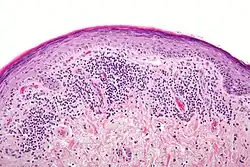

Histopathology

The histologic findings of oral LP can offer strong support for the diagnosis, but are not pathognomonic. Clinical correlation is required. Common histologic findings of oral LP include:[47]

- Parakeratosis and slight acanthosis of the epithelium

- Saw-toothed rete ridges

- Liquefaction (hydropic) degeneration of the basal layer with apoptotic keratinocytes (referred to as Civatte, colloid, hyaline, or cytoid bodies)

- An amorphous band of eosinophilic material at the basement membrane composed of fibrin or fibrinogen.

- A lichenoid (band-like) lymphocytic infiltrate immediately subjacent to the epithelium.

Nonetheless, interpreting the histopathological features of oral LP has been associated historically with high intra-observer and inter-observer variabilities.[66]